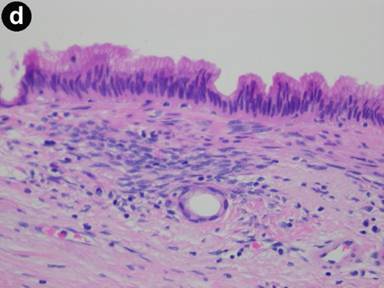

Figure 2. a. CT scan of the abdomen in a 56-year-old female with left upper quadrant pain demonstrates a unilocular pancreatic tail cyst. The cyst wall has variable thickness but does not demonstrate any nodularity. No solid mass was noted. Pseudocyst was suggested in the differential diagnosis of this lesion. b. EUS appearance of the same cyst in A. Thick mucoid cyst content appears granulated on ultrasound, but no visible septations or solid lesions demonstrated. c. Gross surgical resection specimen for the same patient (distal pancreatectomy with splenectomy). No malignancy was detected in this specimen. d. Photomicrograph of a mucinous cystadenoma (H&E, 400x). Columnar mucinous epithelial cells are seen overly ovarian stroma, which is a hallmark of these tumors. |